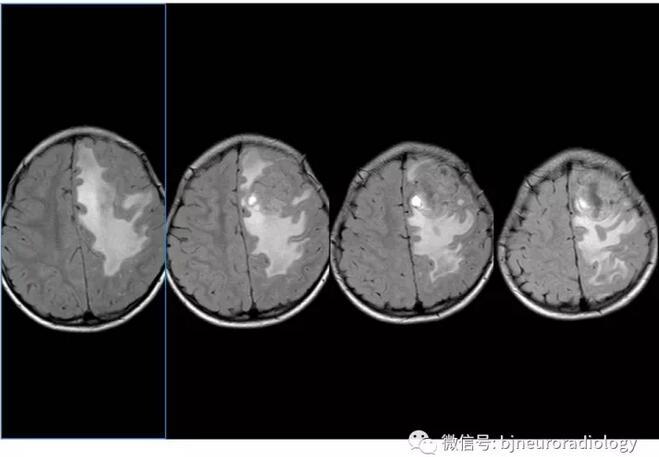

病变位于左额,累及颅骨,边界较清楚,具有脑外肿瘤的特点。平扫与脑组织分界不是非常清晰,皮层挤压征象不明显,应考虑脑内肿瘤的可能性。

脑外肿瘤常见的是脑膜瘤,脑膜瘤常见于成人,强化明显,多引起骨质增生,本病例是儿童病人,并不十分典型。血管周细胞瘤也是以成人为主。因此也需要考虑脑内肿瘤的可能性。